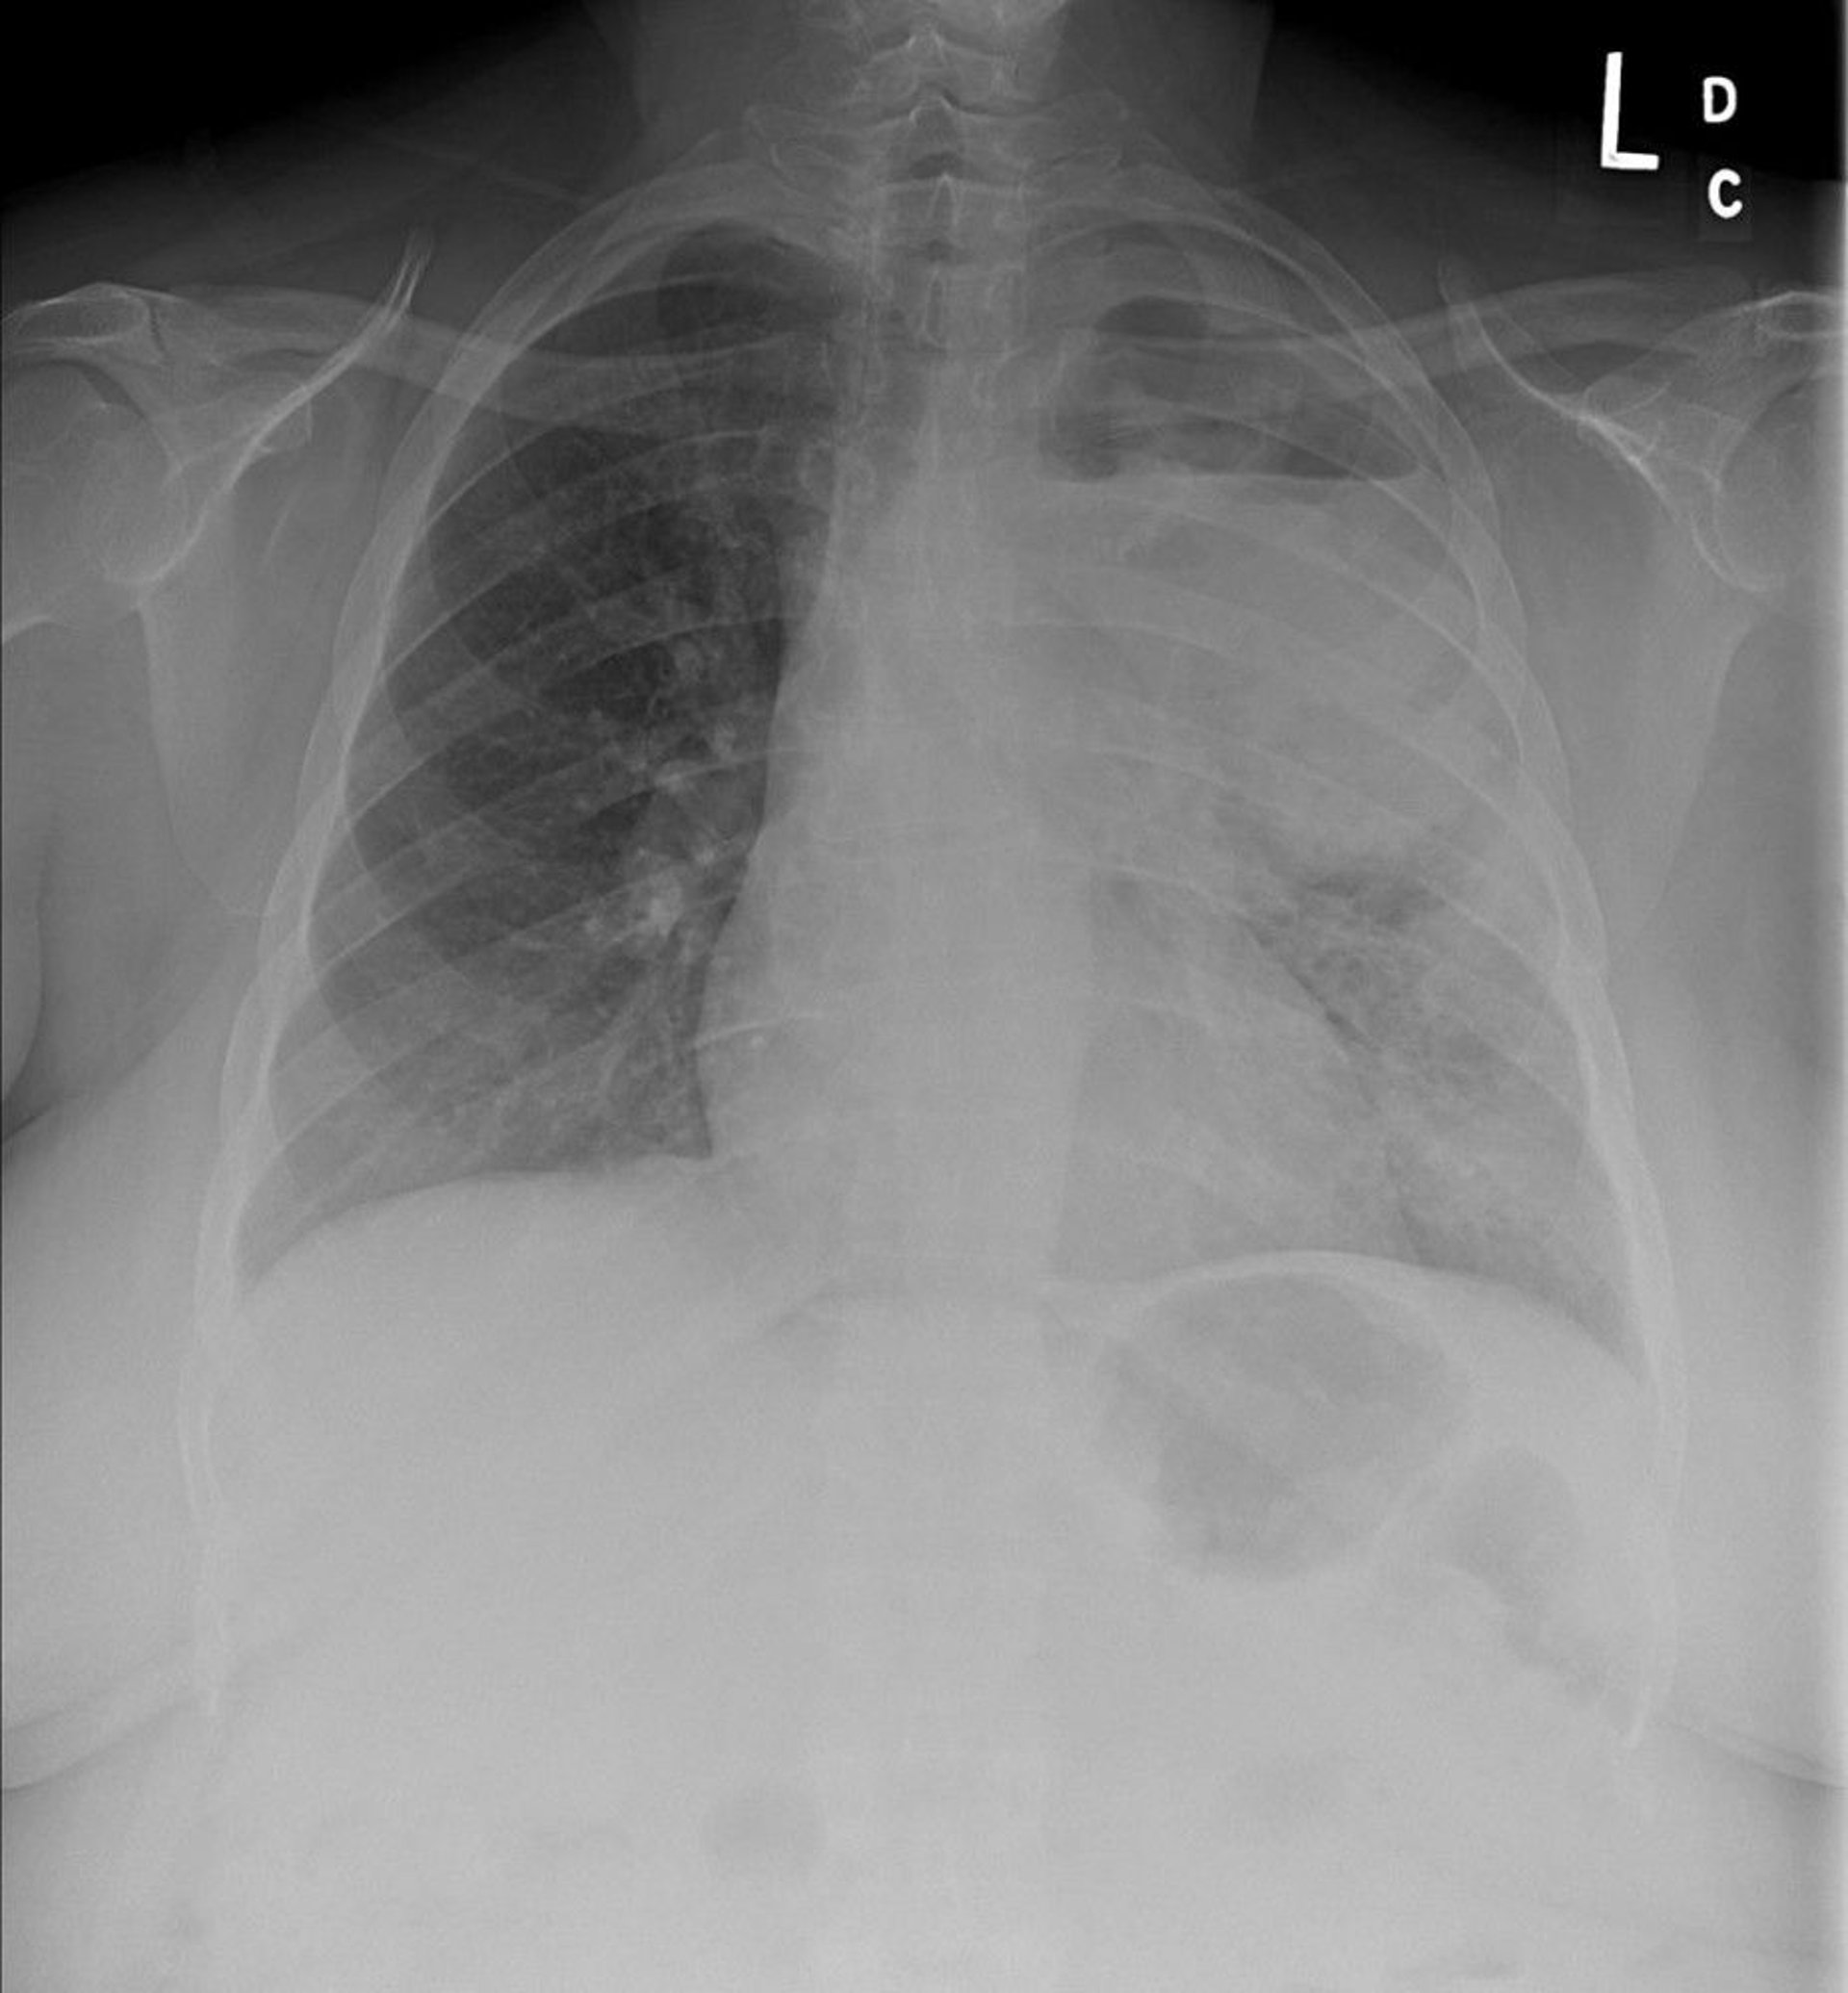

Chest radiography shows a left upper lobe non–small cell lung cancer with mediastinal and left hilar adenopathy. The primary tumor is cavitated and an air-fluid level is present.

Image courtesy of Anne S. Tsao, MD.